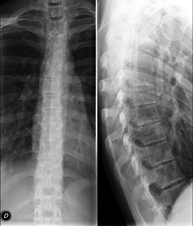

- RX Columna cervical

Tècnica que usa els raigs X a través de la qual s'obtenen imatges de la columna cervical per al seu estudi. Indicacions: traumatisme, dolor cervical. - RX Columna dorsal

Tècnica que usa els raigs X a través de la qual s'obtenen imatges de la columna dorsal per al seu estudi. Indicacions: traumatisme, mal d'esquena. - RX Columna lumbar

Tècnica que usa els raigs X a través de la qual s'obtenen imatges de la columna lumbar per al seu estudi. Indicacions: ciàtica, traumatisme, dolor lumbar. - RX Sacre-còccix

Tècnica que usa els raigs X a través de la qual s'obtenen imatges del sacre i del còccix per al seu estudi. Indicacions: traumatisme, dolor sacre o coccigi. - Telerradiologia columna

Tècnica que usa els raigs X a través de la qual s'obtenen imatges de tota la columna vertebral per al seu estudi, amb la valoració especialment de la presència d'escoliosi i dismetries pèlviques.